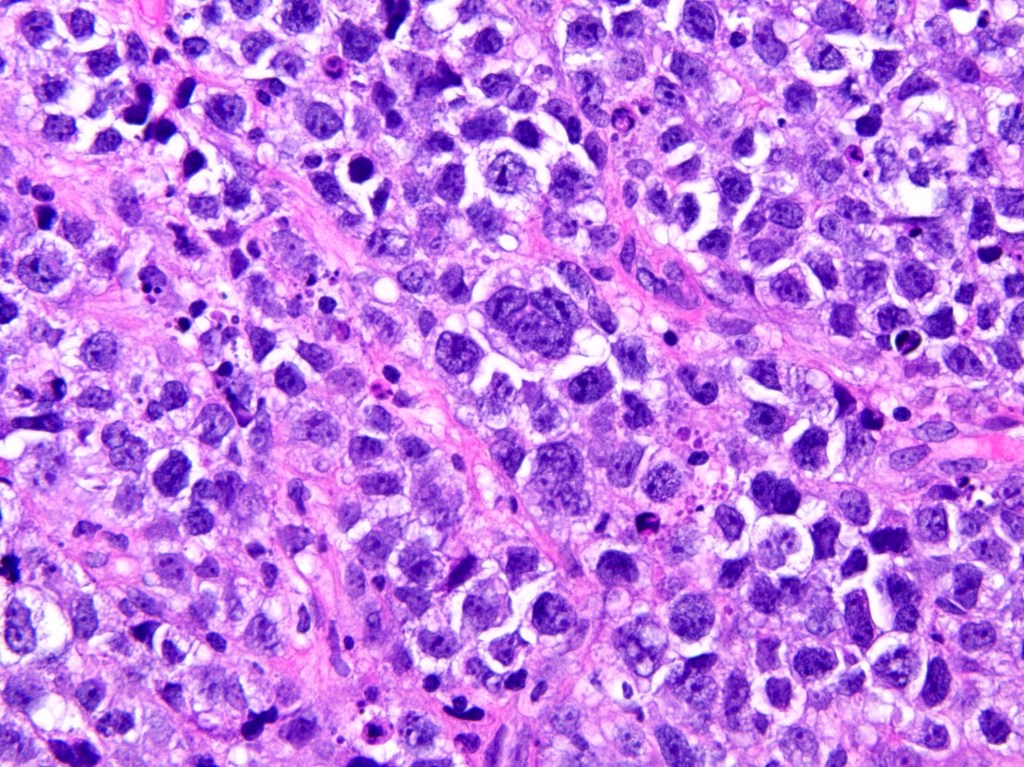

Course 4. Small Round Cell Pattern in Liquid-based Cytology